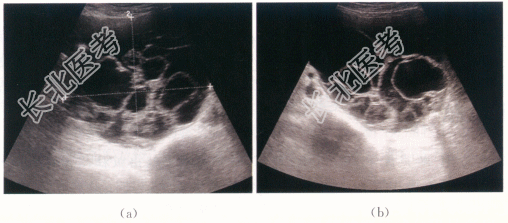

- [材料题] 患者,女性,49岁,因“发现腹胀、腹围增大2个月”就诊。患者自诉近2月来腹胀,自觉腹围增大,否认畏寒发热、腹痛、咳嗽咳痰、咯血、恶心呕吐等不适。绝经3年,绝经后无不规则阴道流血、流液等,既往月经规律,否认痛经、经量增多等不适。体格检查:患者下腹部可扪及巨大包块,上界平脐,质硬,活动度差;宫体触诊不清。阴道通畅;宫颈肥大,无举痛及接触性出血。实验室检查:血常规(-),肝肾功能(-),CA125、CA199(-)。影像资料如下: